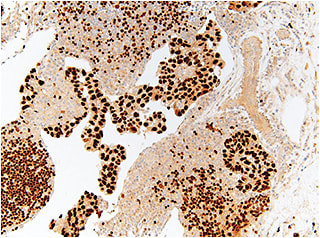

Pathology of an inguinal lymph biopsy was consistent with metastatic carcinoma with clear cell features of gynecological origin (Figure 5). Immunohistochemistry studies were positive for PAX8, a marker used to test for gynecological malignancies (Figure 6). Serum anti-enolase and anti-recoverin antibodies were positive, confirming the presence of paraneoplastic BDUMP as the cause of her recent eye findings.